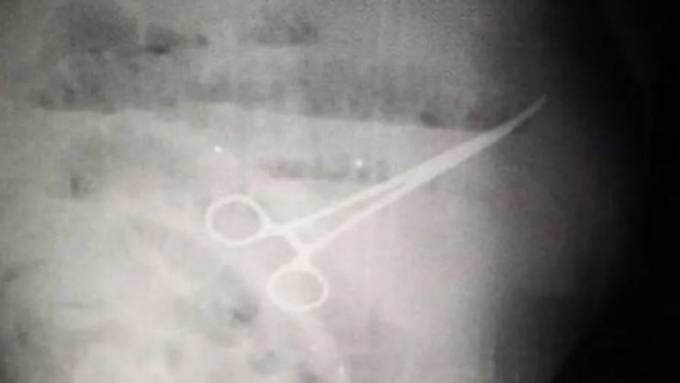

Chiếc kéo trong bụng bệnh nhân qua kết quả chụp x-quang. Ảnh: Newsflash

Bốn ngày sau ca mổ, họ quyết định chụp X-quang cho Chavez và phát hiện có một chiếc kéo đã bị bỏ quên trong bụng bệnh nhân. Chavez qua đời sau đó 5 ngày, và hiện gia đình ông đổ lỗi cho nhóm bác sĩ phẫu thuật đã quá tắc trách, gây ra cái chết.